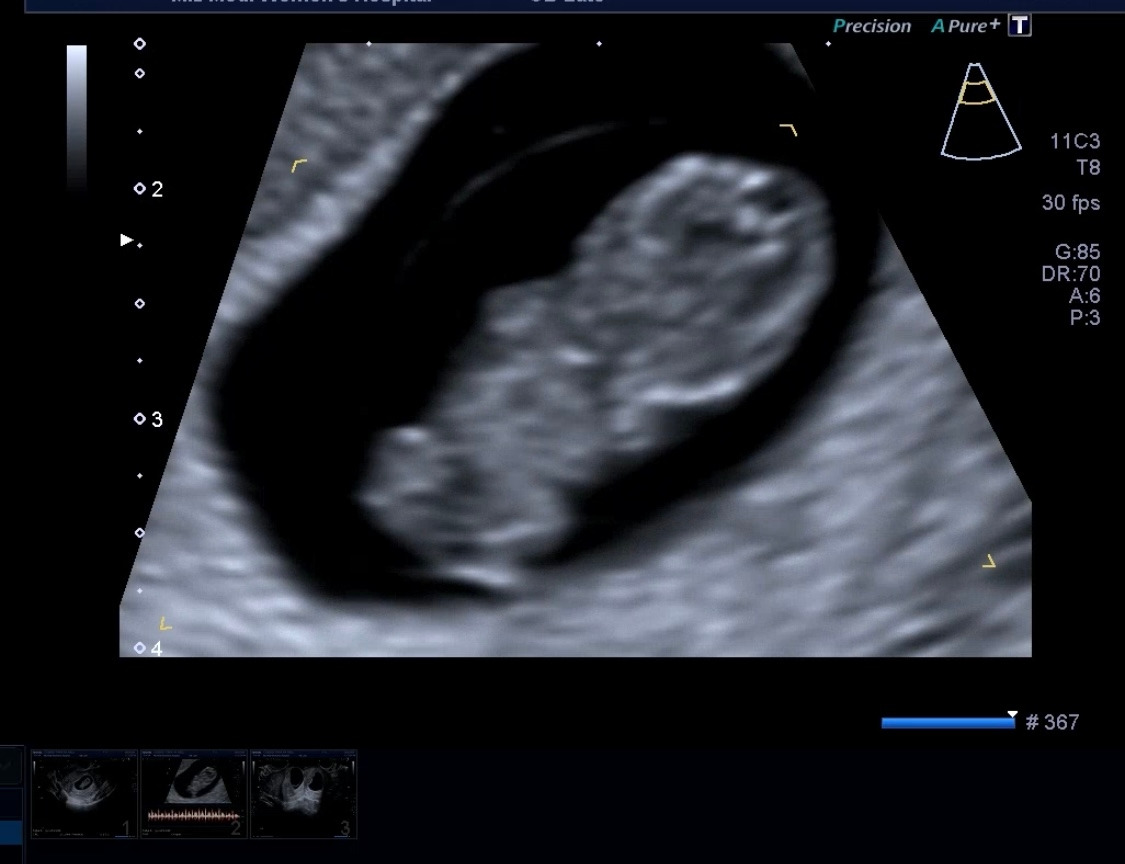

그리고 보여줬던 초음파 속 움직이던 아가의 모습.

이렇게 작은데 팔과 다리 그리고 머리가 꼬물거리는 게 정말 너무 신기했다. 확대 샷까지 보여줘서 자세히 볼 수 있었다. 빨리 태동을 느끼는 그날이 오면 좋겠다. 뭔가 더 다올이와 교류하고 있다는 느낌이 들 것 같다.